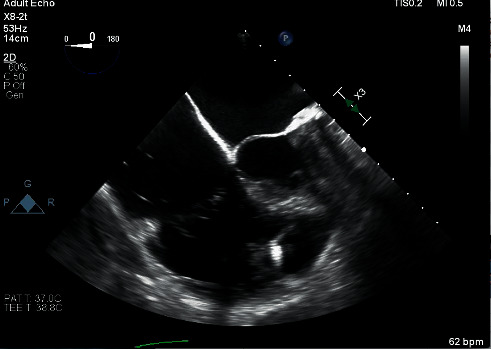

开发无铅心脏起搏器是为了减少与传统经静脉起搏器相关的并发症。虽然这项技术仍然相对较新,但植入的设备越来越多。使用这些装置的患者的围手术期管理一直被低估;因此,我们试图增加有限的知识体的围手术期管理的患者无铅心脏起搏器。一位老年女性患者,因心动过速-心动过缓综合征伴有间歇性完全性心脏传导阻滞,使用Micra VR经导管起搏系统无铅心脏起搏器,因严重三尖瓣返流,计划进行选择性三尖瓣置换术。根据电生理学家的时间安排,在手术前几小时进行起搏器检查;该设备保持在其编程的VVIR模式,并且预期即将进行的手术,基本频率从每分钟60次增加到每分钟80次。在术前评估时,麻醉师要求电生理小组在术中待命,因为担心在起搏器依赖的情况下过度敏感和/或心率反应性起搏可能发生不良的心动过速。外科医生在心脏手术期间使用单极电。尽管患者术前在重症监护病房有起搏器依赖的证据,但术中心电图和动脉内侵入性监测未发现电磁干扰导致过感或速率调节。关于无导线心脏起搏器围手术期管理的循证指南尚不存在。随着这些设备变得越来越普遍,进一步的评估将至关重要,以确定现有的指导方针是否适用于传统经静脉起搏器的围手术期管理。

Leadless cardiac pacemakers were developed to reduce complications associated with conventional transvenous pacemakers. While this technology is still relatively new, devices are increasingly being implanted. The perioperative management of patients with these devices has been underreported; we thus seek to add to the limited body of knowledge of perioperative management of patients with leadless cardiac pacemakers. An elderly female patient with a Micra VR transcatheter pacing system leadless cardiac pacemaker placed for tachycardia-bradycardia syndrome with intermittent complete heart block was scheduled for elective tricuspid valve replacement for severe tricuspid regurgitation. Pacemaker interrogation was performed several hours prior to the scheduled surgery based on the electrophysiologist's availability; the device was kept in its programmed VVIR mode, and the base rate was increased from 60 to 80 beats per minute in anticipation of the upcoming surgery. Upon preoperative evaluation, the anesthesiologist asked that the electrophysiology team be placed on standby intraoperatively due to the concern that either oversensing in the setting of pacemaker dependence and/or undesirable tachycardia from rate-responsive pacing could occur. The surgeon used monopolar electrocautery for the duration of the cardiac surgery. Despite the patient having evidence of pacemaker dependence in the intensive care unit preoperatively, no electromagnetic interference leading to oversensing nor rate modulation was detected during intraoperative electrocardiographic and intraarterial invasive monitoring. Evidence-based guidelines regarding perioperative management specifically of leadless cardiac pacemakers do not exist. As these devices become more prevalent, further evaluation will be paramount to determine whether existing guidelines for perioperative management of conventional transvenous pacemakers apply.